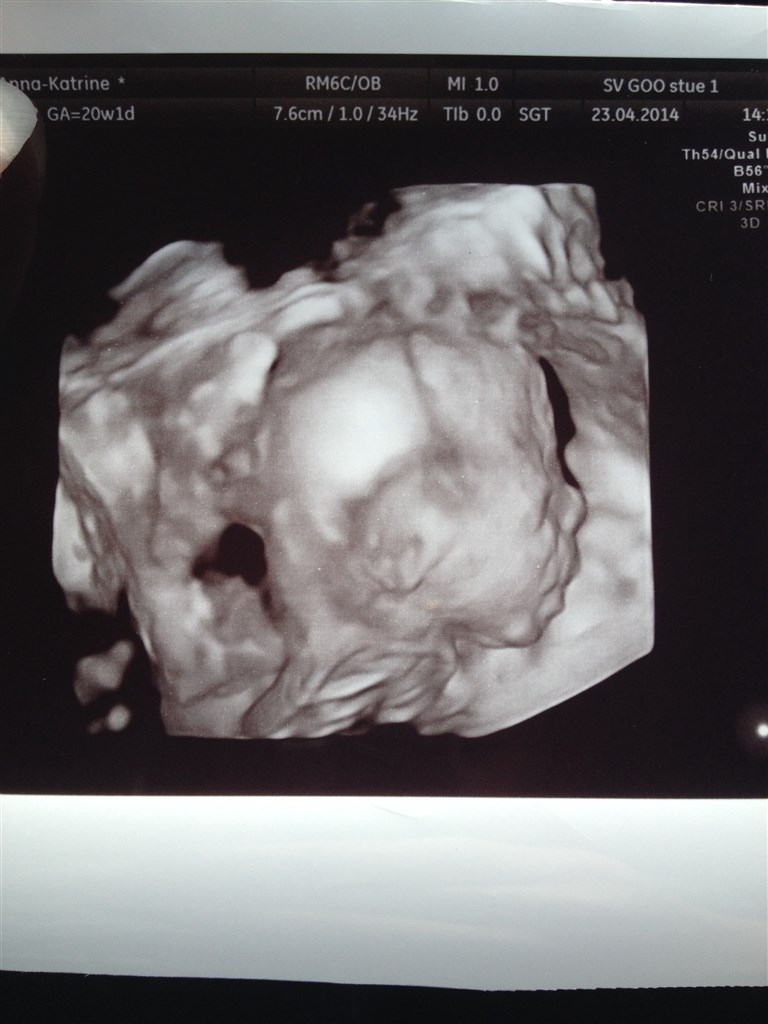

I får lige et billede med fra MD-scanning for 14 dage siden af vores baby Karla

Vedhæftede fotos (klik for at se i fuld størrelse)